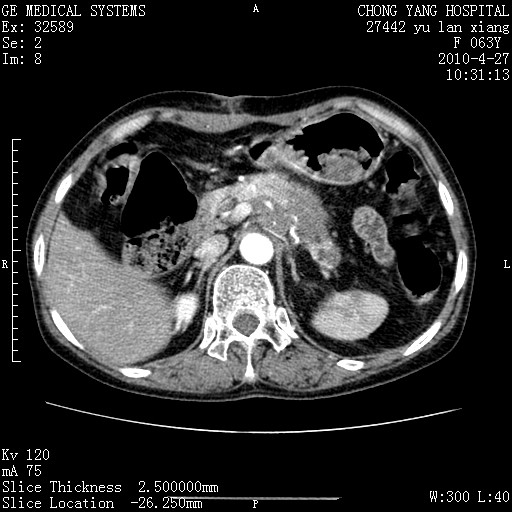

标题: CT26066:F63Y 上腹正中压痛半月,CA199:7400u/ml,MR示胰腺炎伴 [打印本页]

标题: CT26066:F63Y 上腹正中压痛半月,CA199:7400u/ml,MR示胰腺炎伴

胰腺癌侵犯腹腔动脉干-分支、胃壁、左侧膈肌伴胰周及腹膜后淋巴结转移、胆囊切除术后。

胰腺癌侵犯腹腔动脉干-分支、胃壁、左侧膈肌伴胰周及腹膜后淋巴结转移、胆囊未显影。